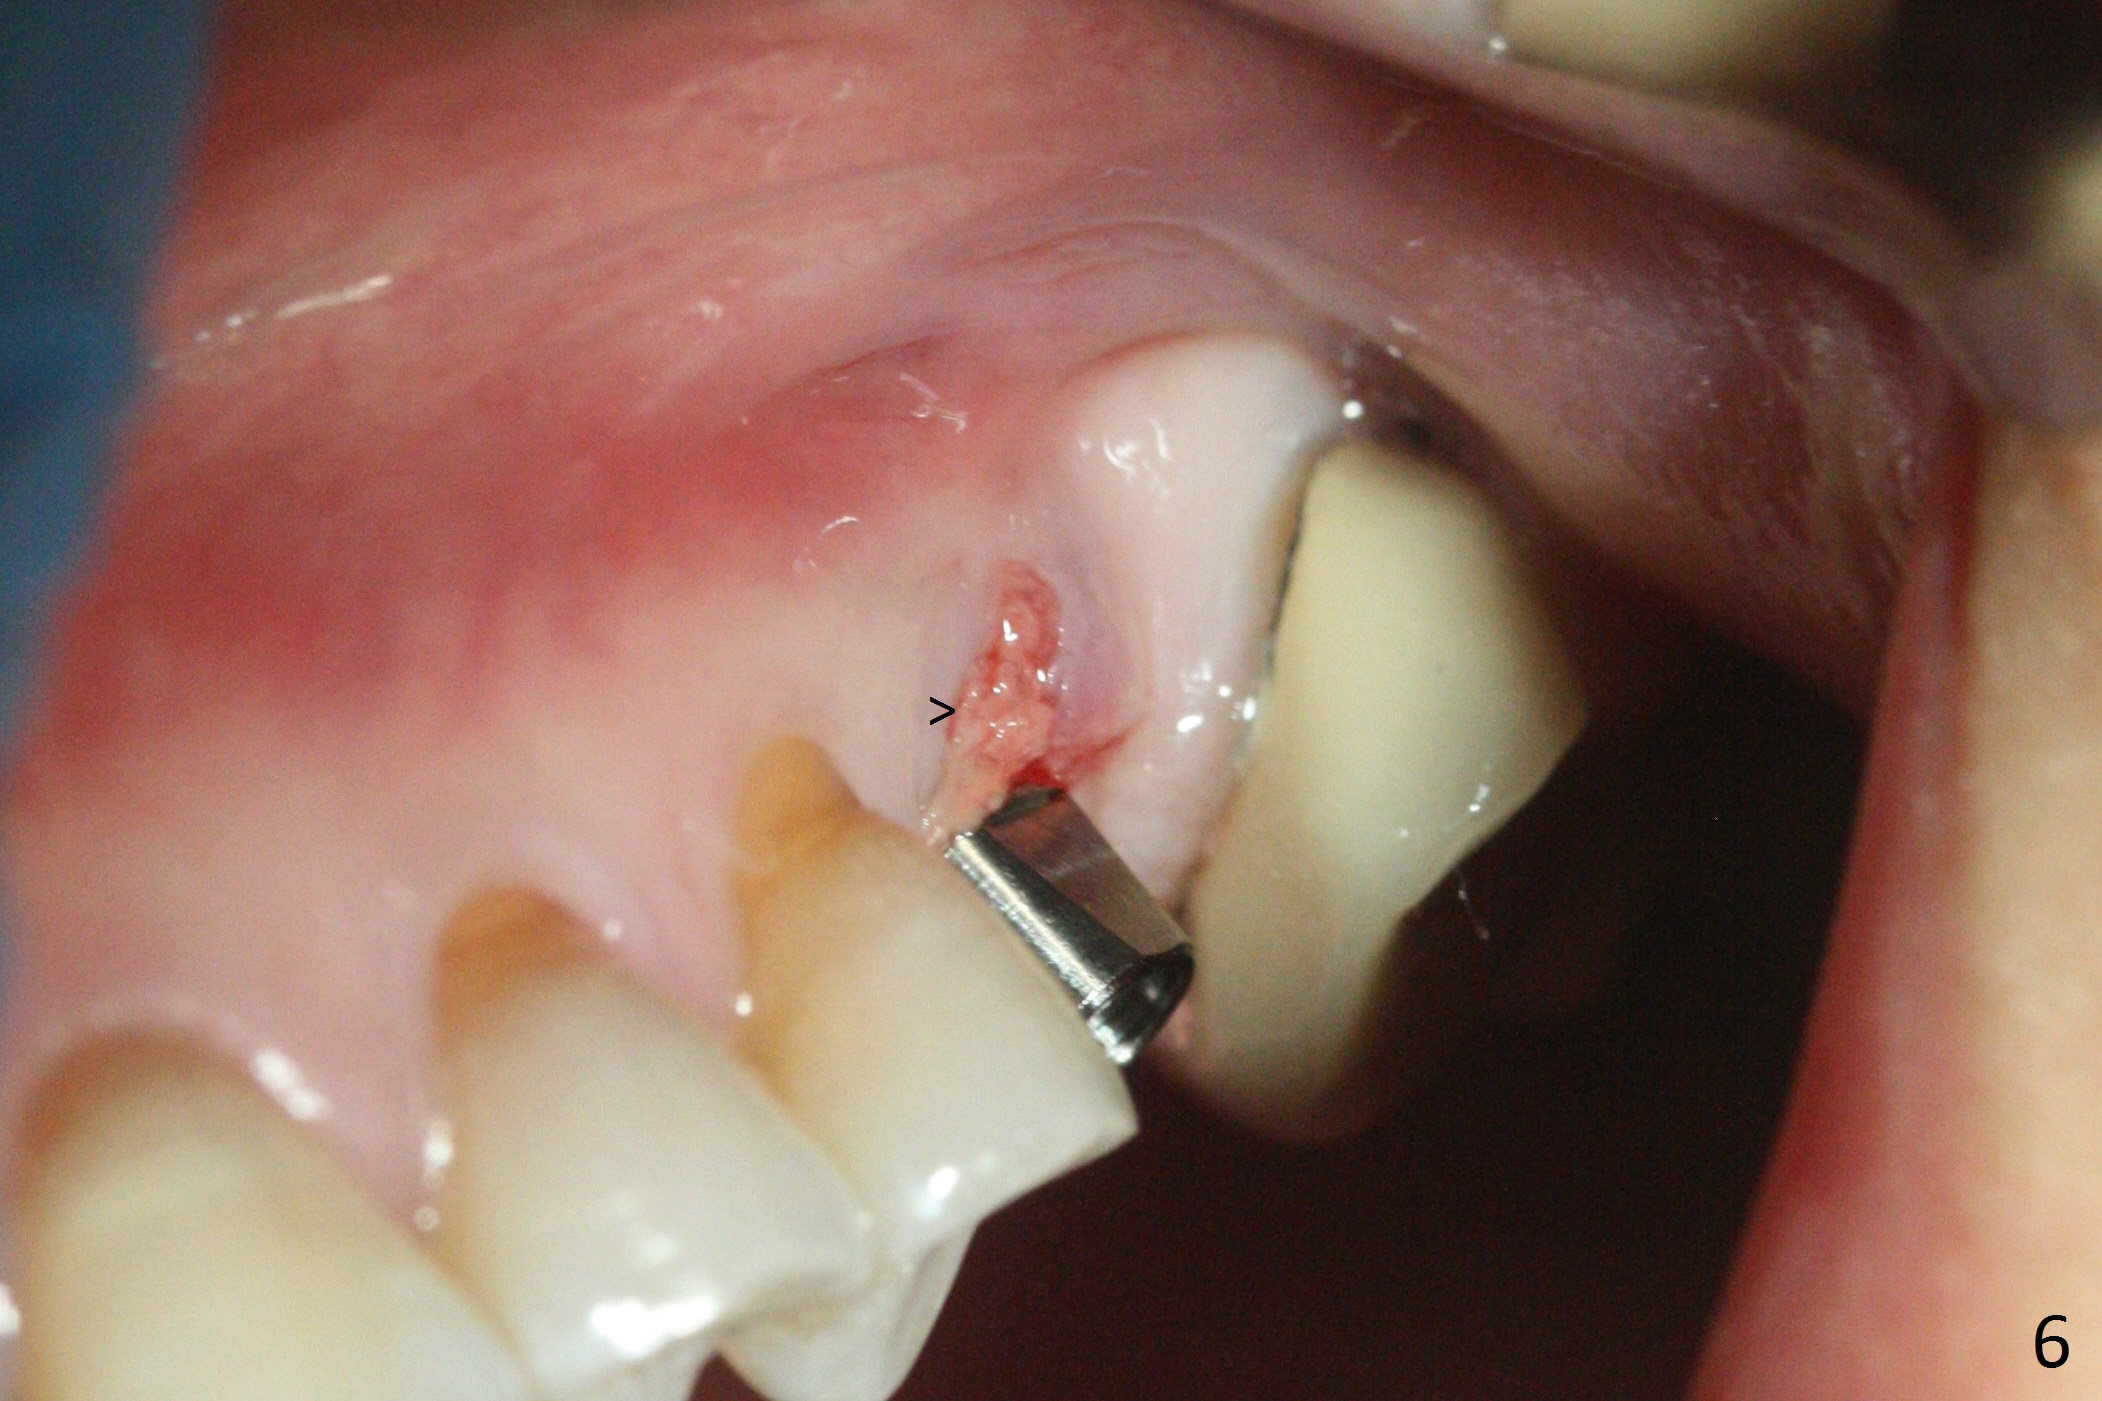

Magic Split is used to start access (flapless) and initial bone expansion at #14. The split does not go deep, since bone density is high in the deep portion. A 1.6 mm drill has to be used for 13 mm (Fig.1). Note the low bone density in the distobuccal socket (*). Later the osteotomy extends to 15 mm (gingival level). After 3.8 mm Magic Drill (MD) for 15 mm, a 4x11 mm dummy implant is placed with insertion torque of 60 Ncm (implant motor, Fig.2). After 4.3 mm MD, a 4.5x11 mm IBS implant is placed with insertion torque of 60 Ncm for implant motor >40 Ncm for torque wrench (Fig.3). The implant seems to be placed deep, but the buccal plate feels to be low. Following bone graft buccally, especially distobuccal (Fig.4,5 ^), a 5x4(3) mm abutment is placed. The buccal gingiva is torn during bone graft (Fig.6 >). Periodontal dressing is applied around the abutment (for increased retention) for wound protection.